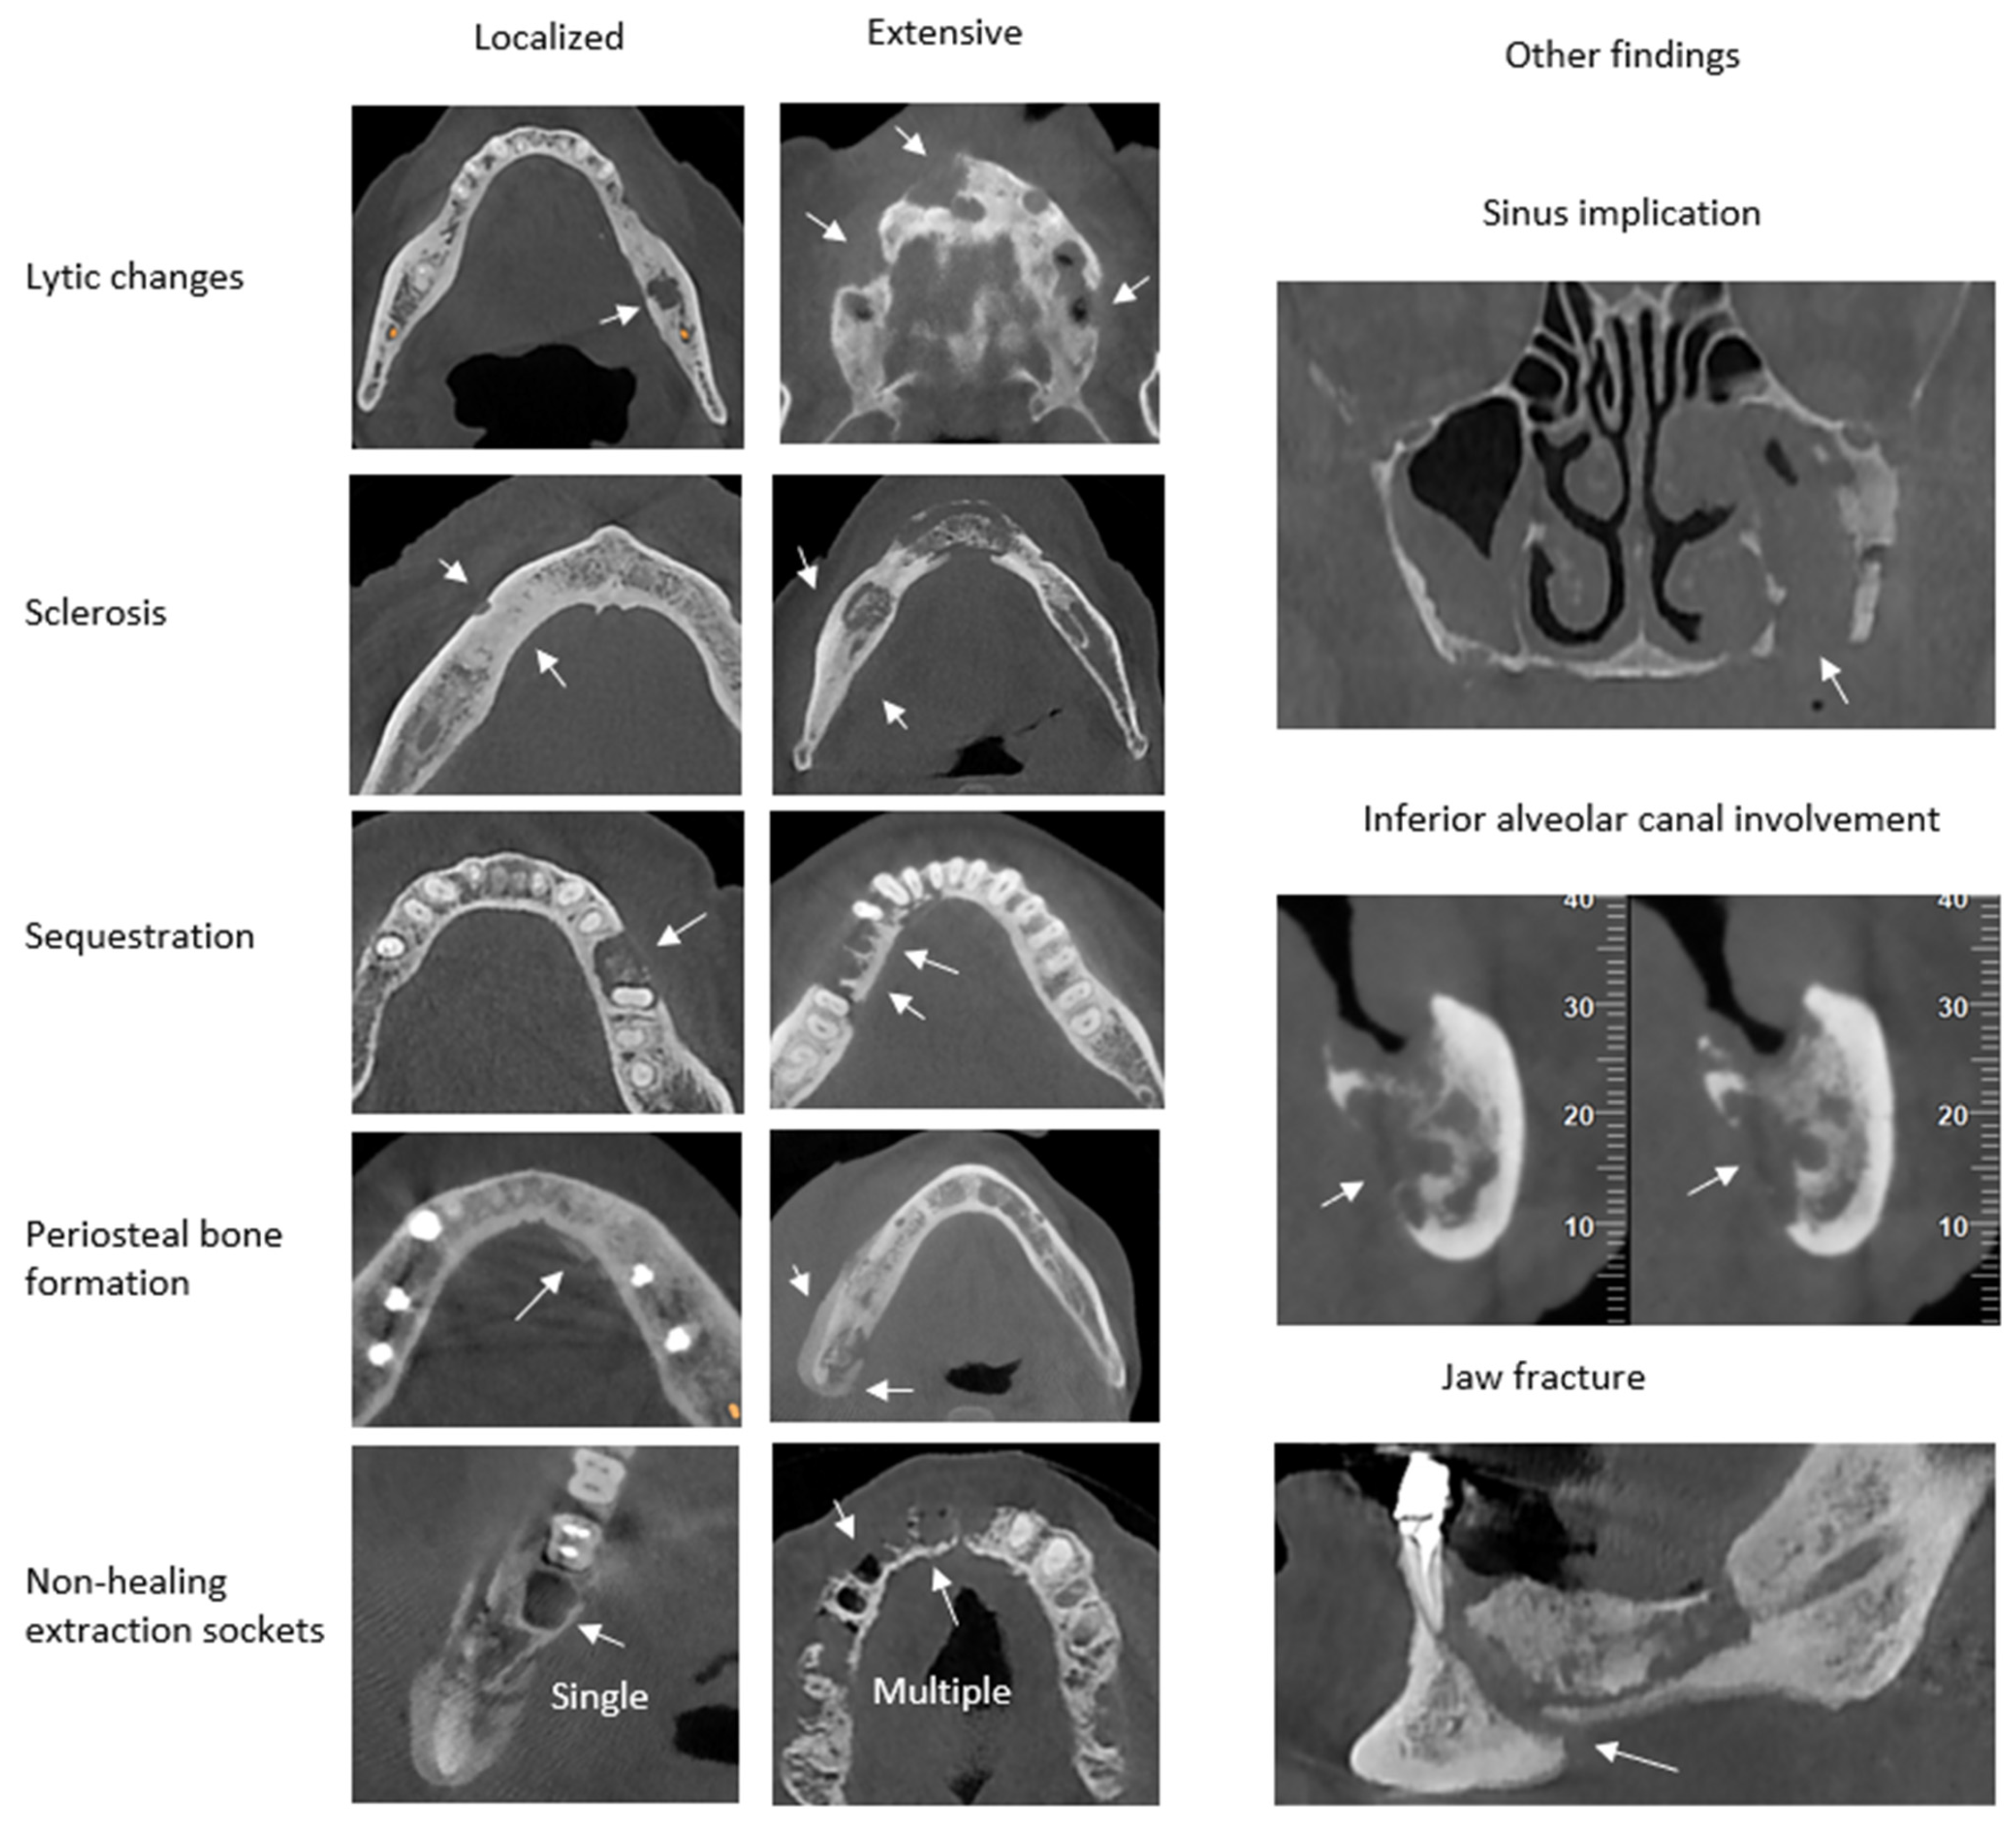

The CRIm is based on the Composite Radiographic Index (CRI) introduced by Walton K [7]. The CRI evaluates four radiologic parameters: lytic changes, sclerosis, periosteal bone formation, and sequestration. To improve the existing CRI, two parameters common in the above-mentioned diseases were added to the CRIm. This addition resulted in eight radiologic features that can be classified and evaluated: lytic changes, sclerosis, periosteal bone formation, sequestration, non-healing extraction sockets, and other findings. Other findings include maxillary sinus implication, inferior alveolar canal involvement, and jaw fracture [9]. Lytic changes, sclerosis, periosteal bone formation, and sequestration are scored as follows: (0) for absence, (1) for localized lesions extending up to 1 cm, and (2) for extensive lesions extending 1 cm or multiple lesions. Extraction sockets showing no sign of healing are evaluated only if they are near the lesion, and are scored as follows: (0) absent, if no sockets are present; (1) localized, for the presence of one socket; and (2) extensive, for the presence of multiple sockets. The other findings are individually scored as (0) when absent and (1) when present [9] (Figure 1).

Figure 1.

Examples of CRIm scoring for severity of radiologic findings in CBCT images.